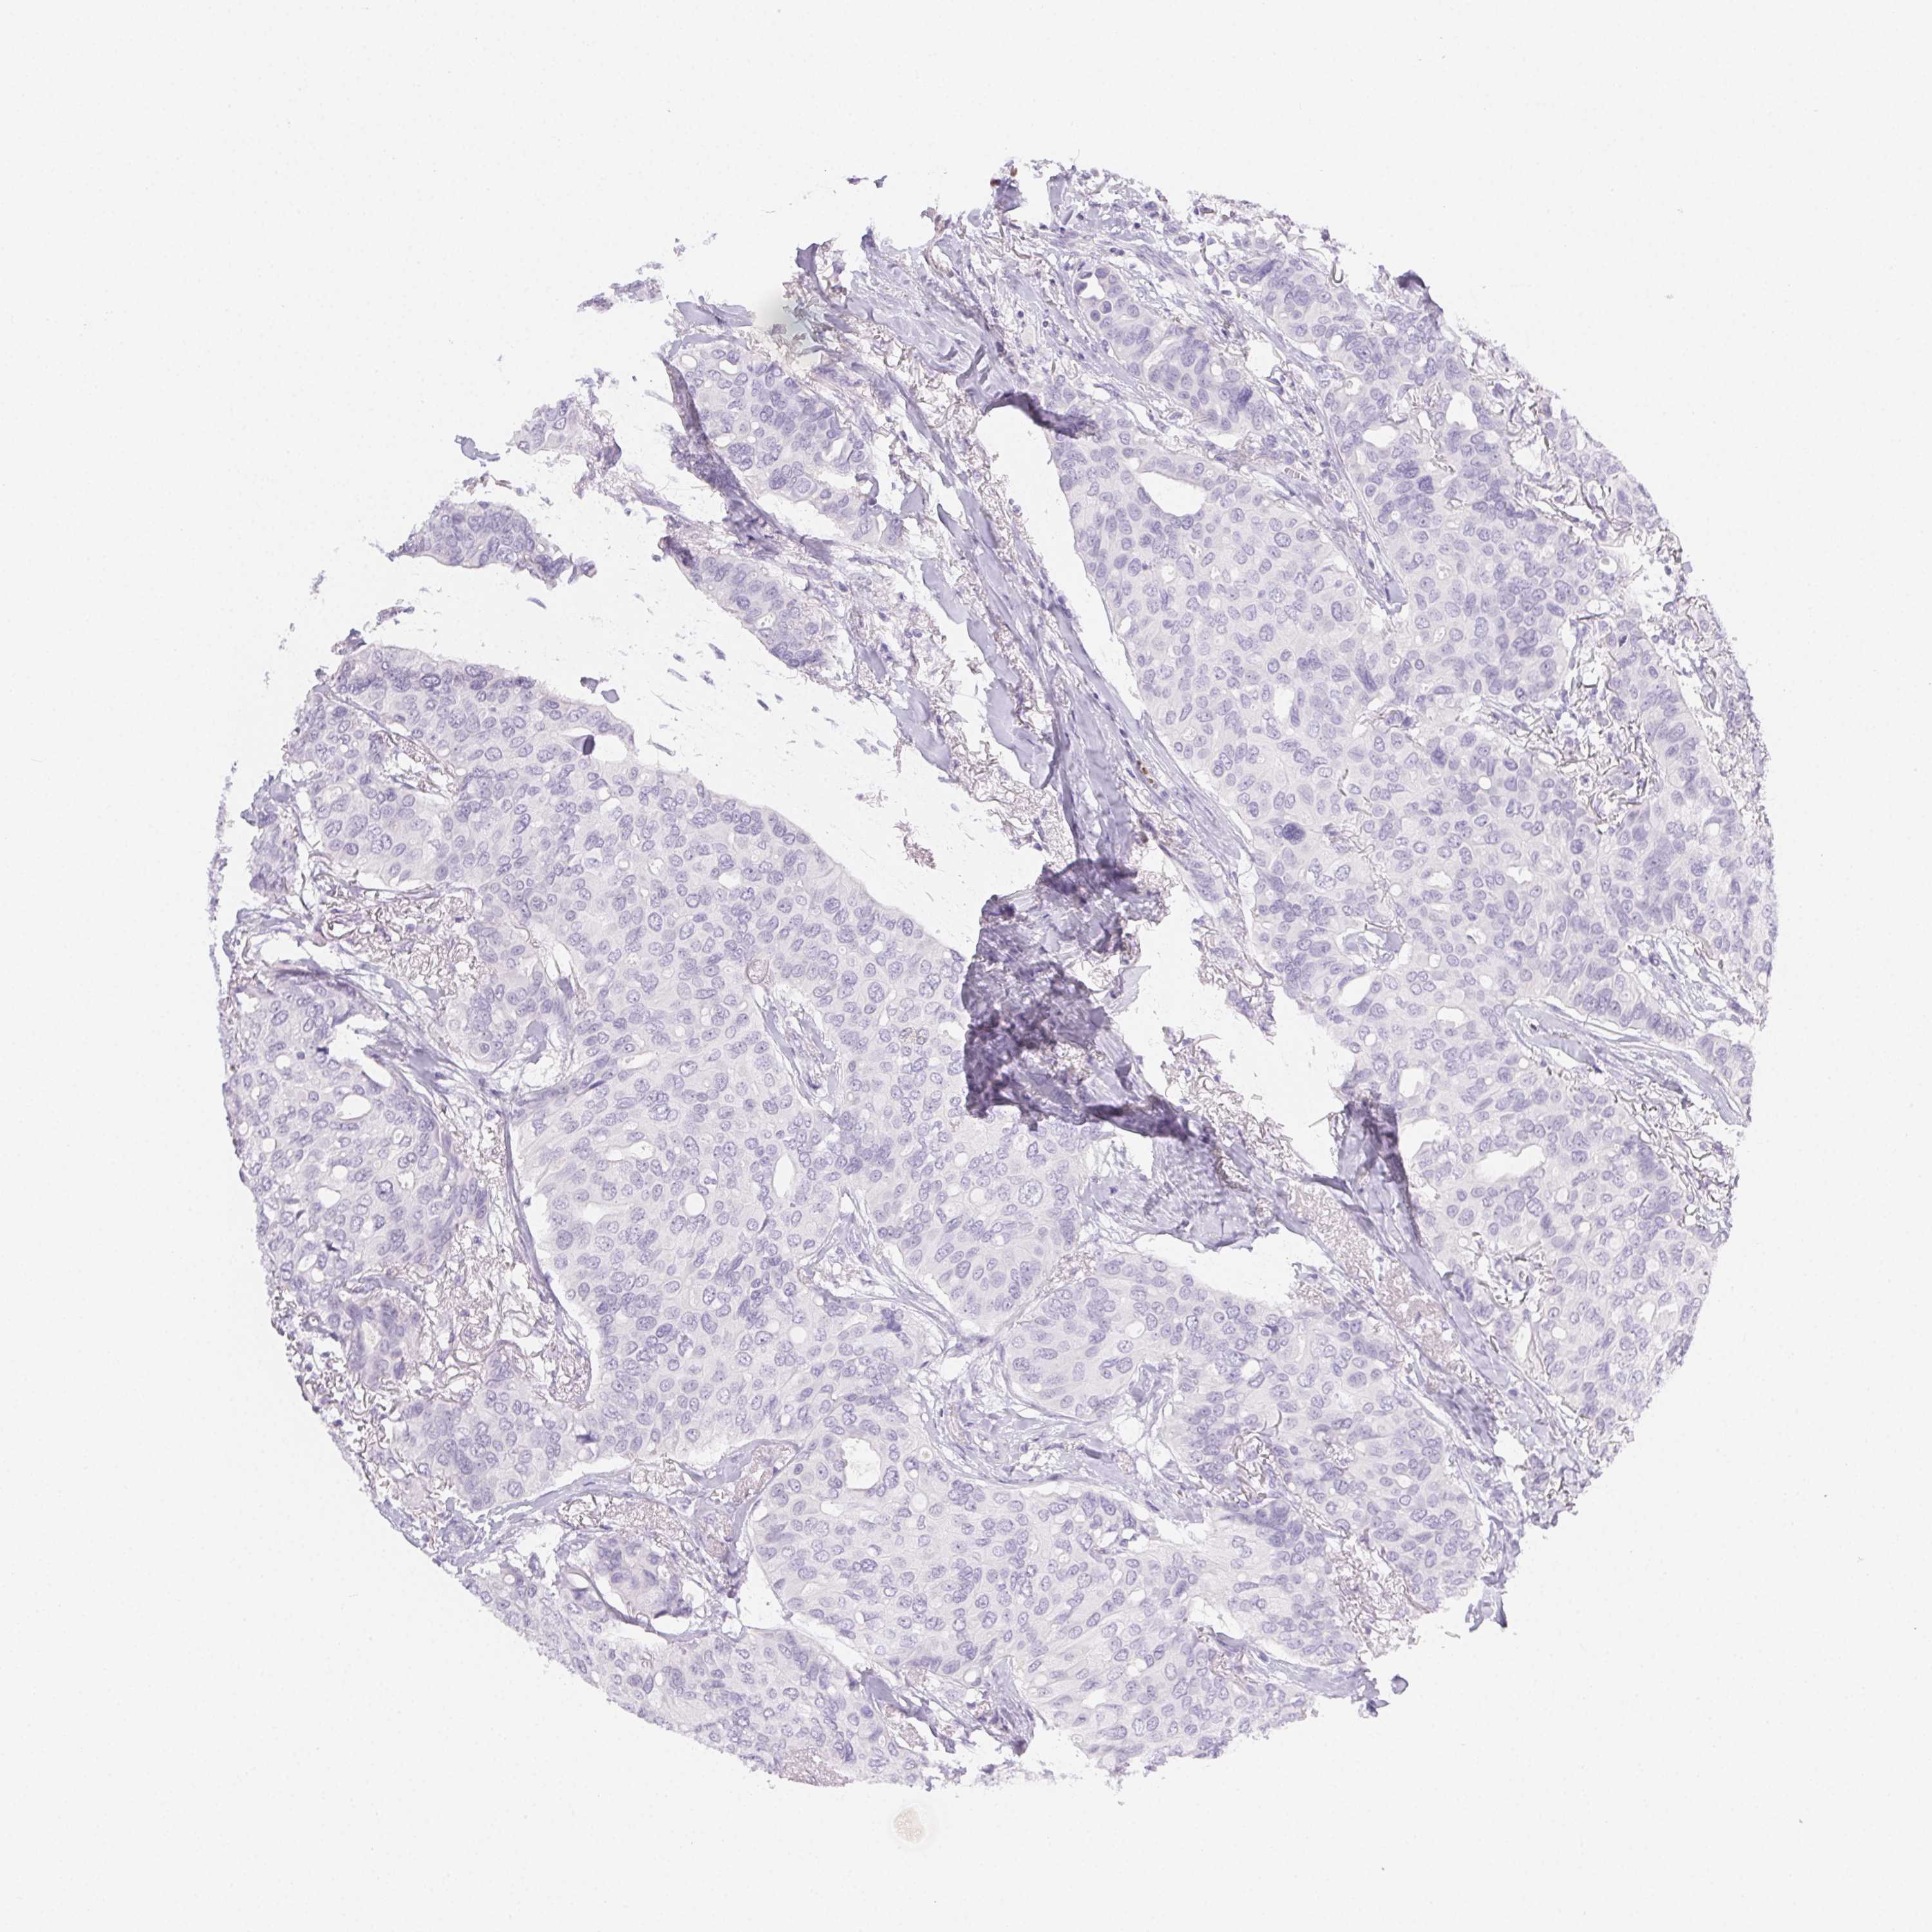

CANCER BREAST CANCER Show tissue menu

BRCA TCGA BRCA VALIDATION PROTEIN EXPRESSION

Breast cancer

Human cancer

Breast invasive carcinoma